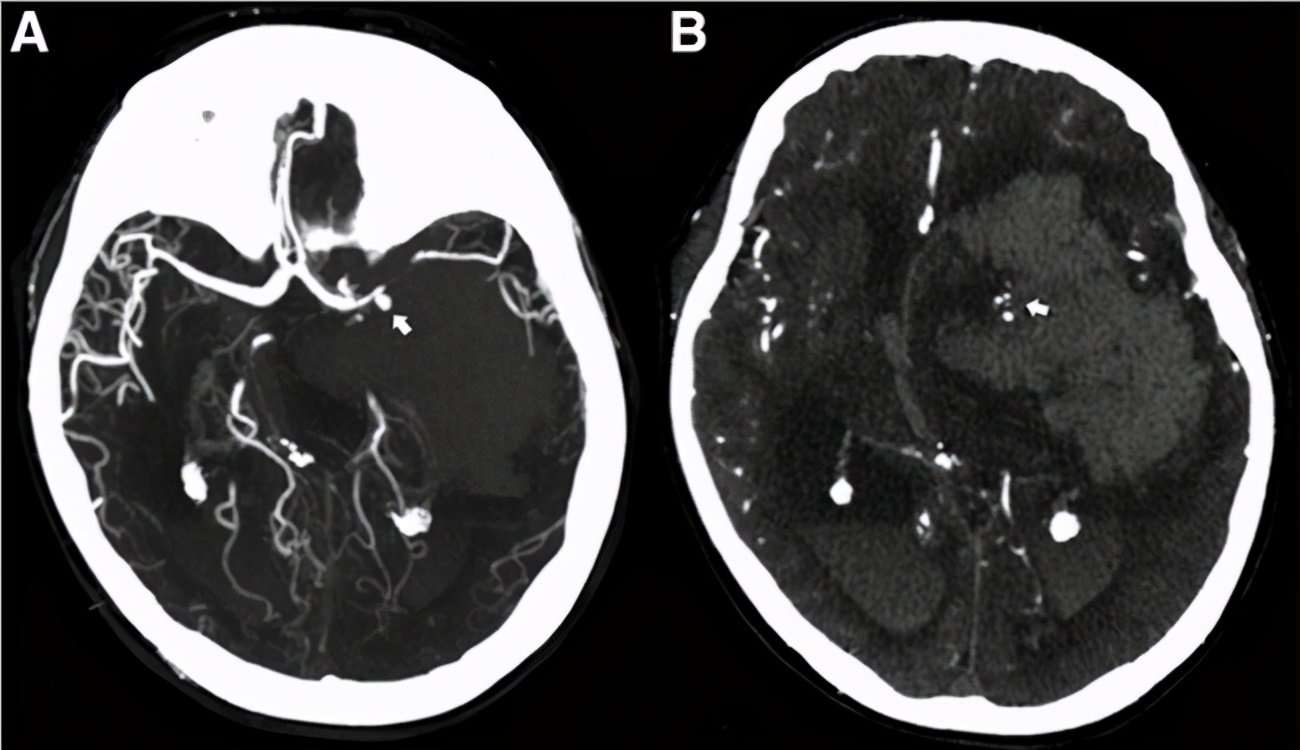

由于自身特殊的解剖位置,腹膜后间隙后壁是髂腰肌,前壁有腹膜覆盖,包括肾脏、肾上腺、输尿管、下腔静脉等。病人大多在病情发展较晚期就诊,同时往往有周围血管、脏器侵犯。需要结合包括彩超、CT增强、MRI、血管造影来对对肿瘤本身及“周围环境”有清晰的认识。

血管造影(DSA)作为补充检查对于腹膜后肿瘤有时起到至关重要的作用。不仅可以显示肿瘤的血流供应情况,对于肿瘤周围的血管毗邻有清晰的认识在研究中,我们发现主要侵犯的血管包括下腔静脉(IVC),腹主动脉,髂血管,肠系膜上动脉。

对于一些直径较大的,血供丰富且单一的肿瘤,术前对肿瘤栓塞可以缩小肿瘤体积,减少术中出血,降低手术难度。同时应当警惕栓塞血管后导致肿瘤坏死,刺激肿瘤细胞再次增殖,加快肿瘤的生长。